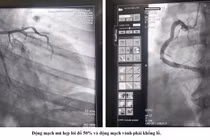

Kíp can thiệp do Ths.BS Đinh Danh Trình, Trưởng khoa Tim Mạch, Bệnh viện Bãi cháy cùng ê-kíp thực hiện. Kết quả chụp mạch cho thấy: Động mạch vành phải hẹp 95%; Động mạch liên thất trước tắc gần hoàn toàn đoạn 1–2.

Đây là tình huống rất nguy kịch, nguy cơ ngừng tim trên bàn can thiệp bất cứ lúc nào. Các bác sĩ đã nhanh chóng xử trí, đặt 01 stent phủ thuốc nhánh động mạch vành phải và 01 stent phủ thuốc ở nhánh động mạch liên thất trước, tái thông dòng chảy mạch vành toàn bộ thành công và cứu sống người bệnh.